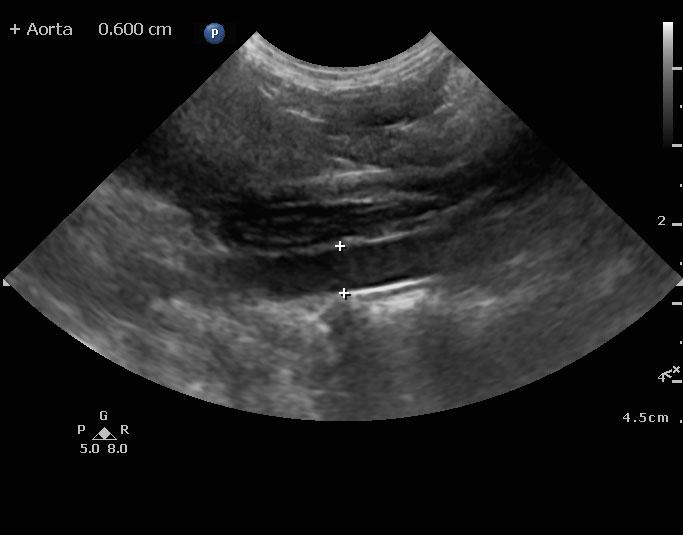

An 8-year-old spayed female Maltese dog was presented for evaluation of severely elevated pre-and post-prandial bile acids. In addition, the patient was positive for Rocky Mountain spotted fever. Seizure activity was present in the history